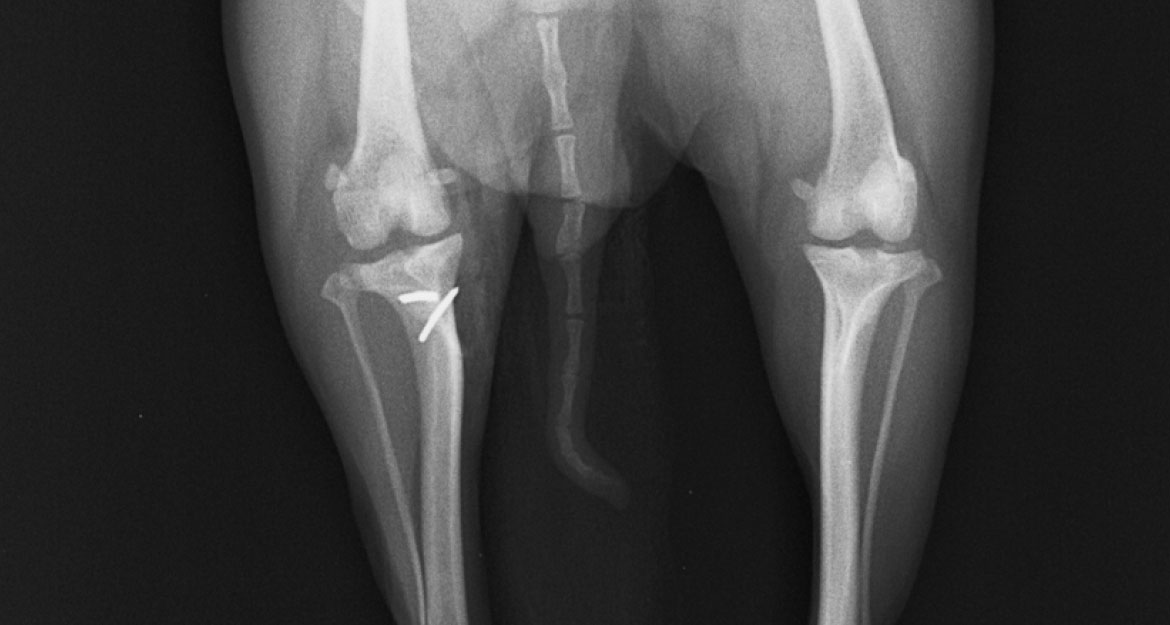

外方脱臼(両後肢)

-

Before

外方脱臼によりX脚に -

After

膝蓋骨が整復され、脚も真っ直ぐになりました